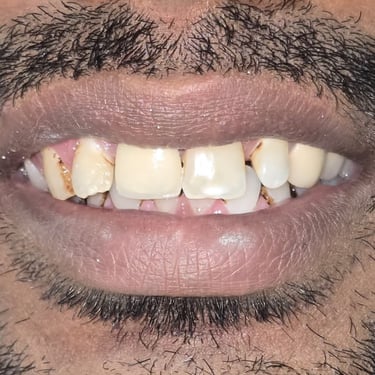

Step 5: Crown / Cap Placement

Finally, a ceramic cap (crown) was placed to restore the tooth’s shape, function, and smile aesthetics. The patient’s smile was completely rehabilitated, boosting confidence.

Before & After Photographs

This visual journey helps patients understand the importance of timely dental treatment and how a fractured tooth can be saved.

This case demonstrates how a fractured tooth due to trauma can be successfully treated with Root Canal Treatment, fiber post, core build-up, and crown placement. Timely treatment not only saves the natural tooth but also restores function, aesthetics, and confidence.